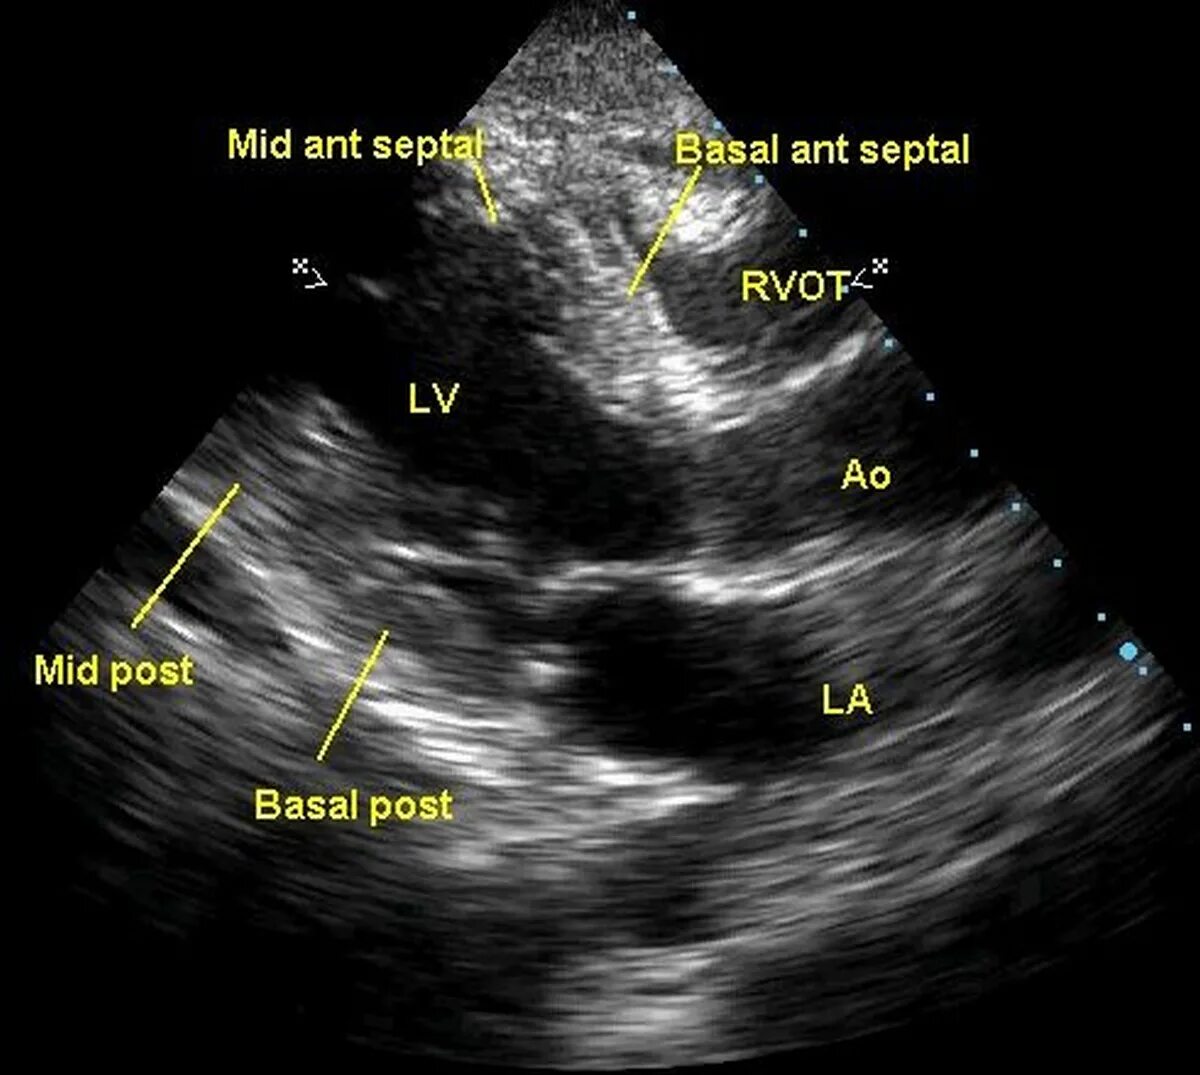

Гипокинез передних сегментов